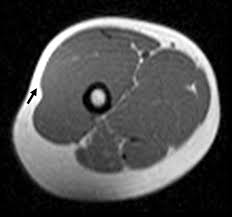

ㄷ. 근육의 섬유

- 근원섬유(sarcomere) : 근섬유의 기본단위

- 근섬유(muscle fiber) : 근육섬유가 근육속막에 의해 모인 다발

- 근섬유다발(fascicle) : 근섬유가 근육다발막에 의해 모인 다발

- 근힘살(muscle belly) : 근육다발막이 근육바깥막에 의해 모인 다발